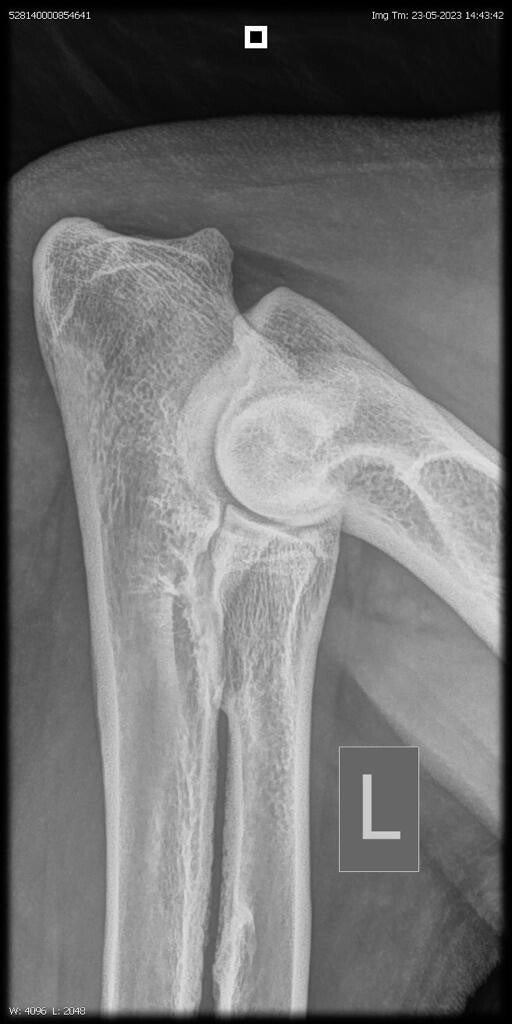

23/06/2023: Röntgenopname ellenbogen + heupen -> geen afwijkingen (heupdysplasie A, ED vrij)